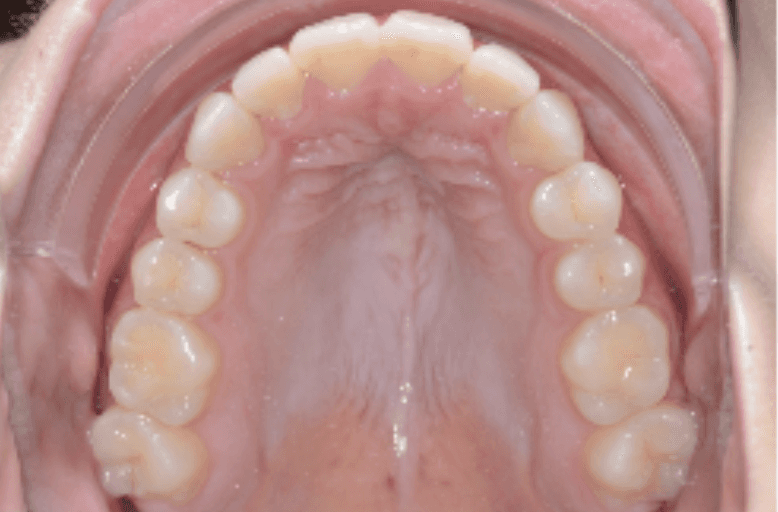

Initial treatment

INTRAORAL